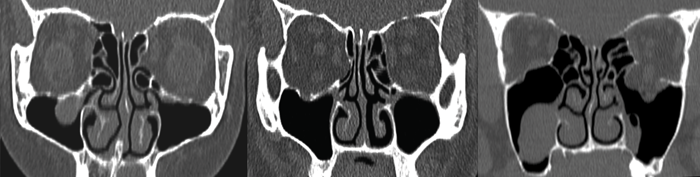

Operative CT - the disease

Most FESS is performed for chronic rhinosinusitis. The scan should have been studied well before surgery, but immediate preoperative review is a final opportunity to recognise a sinonasal mass and avoid the unexpected complications of operating on a vascular tumour or meningo / encephalocoele. Findings of an antrochoanal or frontochoanal polyp must be recognised; dictating a surgical approach to allow complete clearance. Bony changes in a unilateral polyp may indicate an inverted papilloma or neoplasia, necessitating histopathologic analysis.

Juvenile Nasal Angiofiboma.

Meningoencephalocoele.

Endonasal Malignancy.

Lamina Papyracea Defects.